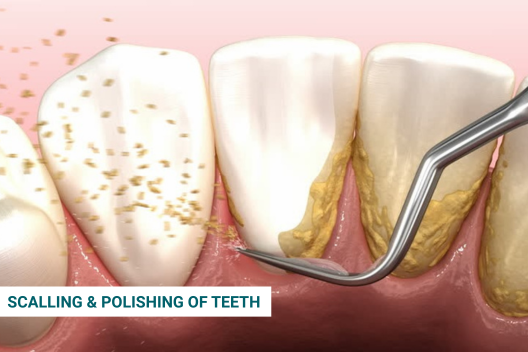

Preventive dental care

Preventive dental care is all about staying ahead of oral health problems before they start. It combines daily at-home practices like brushing, flossing, and using mouthwash with regular dental visits for professional cleanings, check-ups, and screenings. Treatments like fluoride application, dental sealants, and custom mouthguards offer added protection. This proactive approach helps maintain a healthy smile, reduces the risk of cavities and gum disease, and saves you from complex dental procedures in the future.